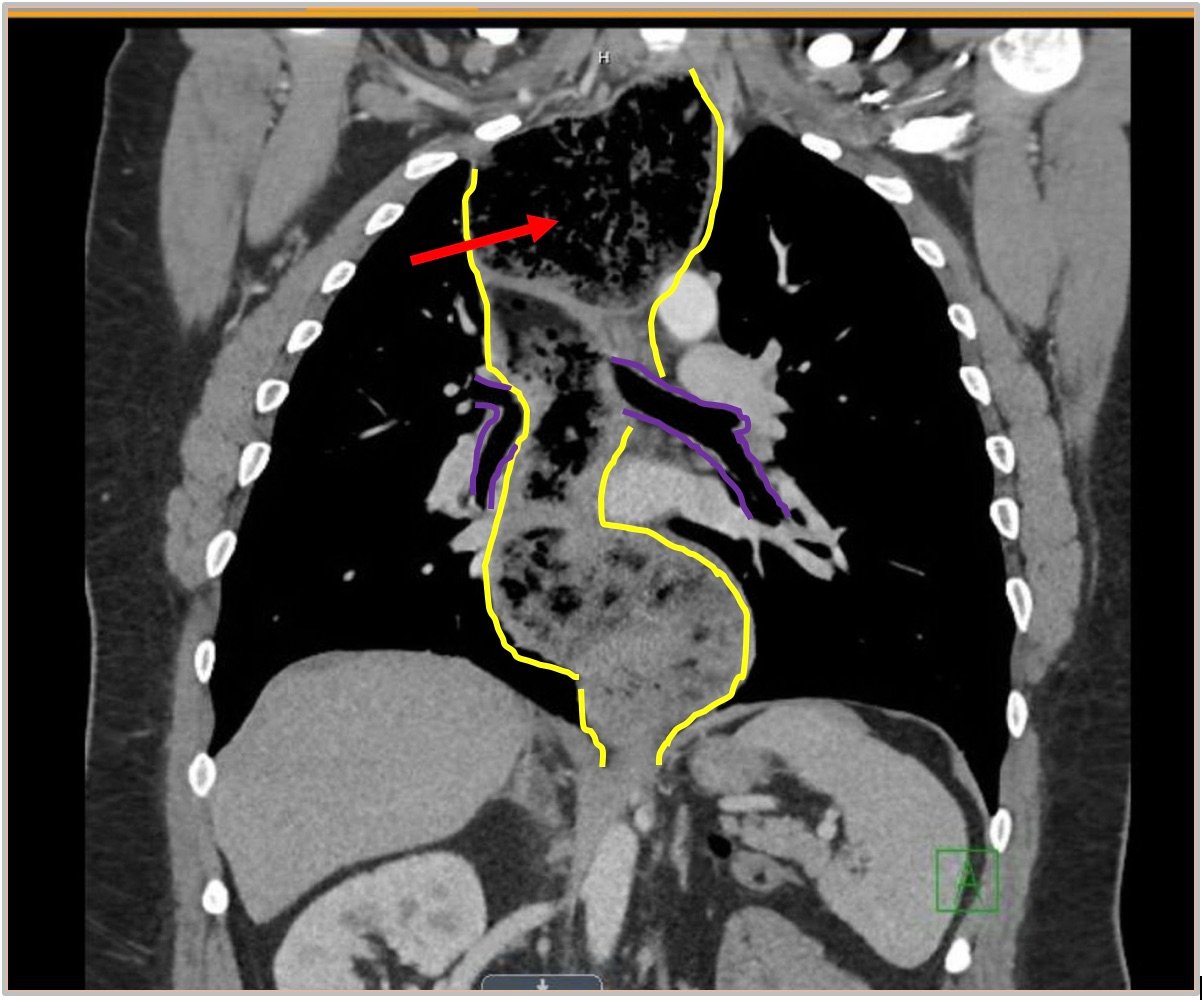

The chest X-ray demonstrated a markedly widened mediastinum (red brackets), raising concern for thoracic aortic aneurysm/aortic dissection, which prompted labs and contrast-enhanced computed tomography (CT) of the chest. The CT revealed a dilated proximal esophagus that narrowed distally (yellow tracing and red arrow), with particulate material, mass-effect on the trachea (purple outline), and bilateral patchy opacities suggesting aspiration. Barium esophagram showed a drastically dilated esophagus filled with contrast (yellow arrow), terminating into the classic “bird’s beak sign” (red arrow) at the lower esophageal sphincter (LES). Esophageal manometry later confirmed achalasia, proving that widened mediastina can have unexpected etiologies.

Achalasia is a rare (prevalence ~0.3-9.5/100,000, increasing with age) digestive disorder characterized by denervation to the distal esophagus, promoting regional aperistalsis and tonic contraction of the LES.1-3 Achalasia most commonly presents as acute, simultaneous dysphagia to both solids and liquids, but can present as heartburn, regurgitation, or even unexplained cough.1-3 A dilated esophagus with narrowing at the LES (“Bird’s Beak Sign”) and delayed esophageal emptying on barium esophagram are pathognomonic for achalasia (sensitivity 90%, specificity 95%),4 as is distal aperistalsis with increased resting LES tone on high-resolution manometry (sensitivity 98%, specificity 96%).5 Pharmacologic LES relaxation may be trialed, but surgical myotomy is usually necessary.1,2,3,6 Our patient underwent laparoscopic Heller myotomy resulting in a dilated, aperistaltic esophagus with no evidence of obstruction and is being followed for continued GERD and dysphagia.